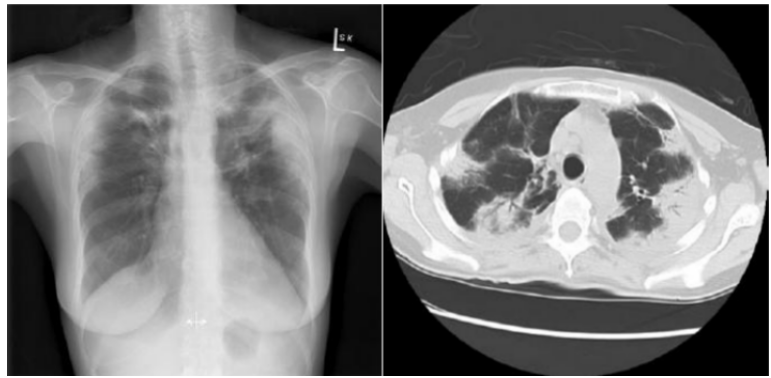

VAP的影像学标准缺乏特异性,例如胸部X线片显示两肺上叶斑片状高密度影,可能是感染,也可能是其他非感染性疾病,如血管炎、嗜酸细胞性肺炎、过敏性肺炎、肉瘤样变、血管炎等。

下图是68岁老年男性患者,因多重耐药结核菌感染行右肺切除,切除后第2日胸部X线片改变,双肺大片实变,最终证实是肺水肿、ARDS。